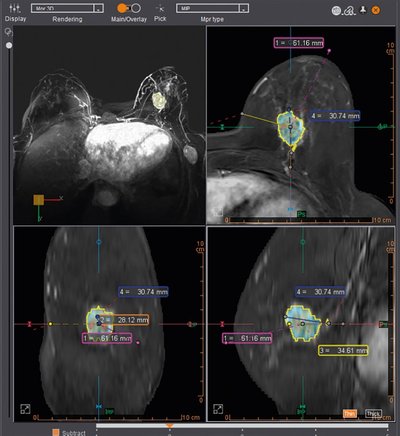

ابزار کامل breastscape شامل Automatic Segmentation ضایعه، محاسبه خودکار حجم، تصحیح حرکت، و گزارشدهی طبق استاندارد BI-RADS. افزونه BreastLoc برای برنامهریزی بیوپسی.

در یک مورد بالینی واقعی، نرمافزار Breastscape توانست با یک کلیک ضایعه مشکوک را به طور خودکار سگمنت کرده و با تحلیل منحنیهای kinetics، به تفکیک دقیق ضایعه سرطانی از فیبروزادنوم کمک کند و نیاز به مداخله غیرضروری را برطرف سازد.